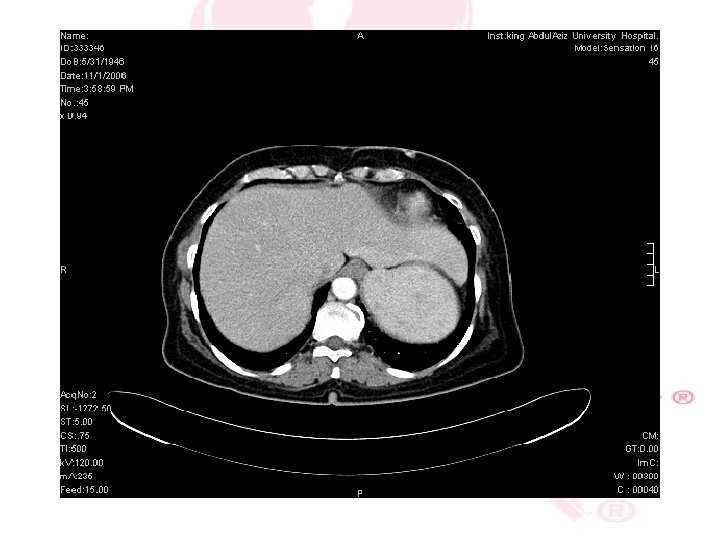

CT SCAN CHEST , ABDOMEN &PELVIS